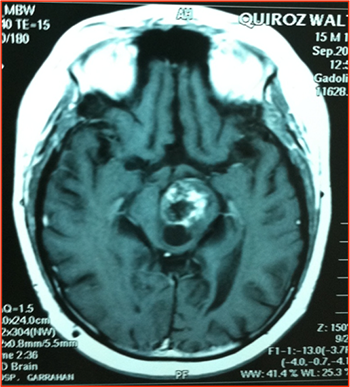

Figura 2:

IRMN T1. Imagen atípica en tumor difuso de protuberancia. Con gadolinio tiene un comportamiento no habitual con refuerzo solo en la parte posterior de la misma.